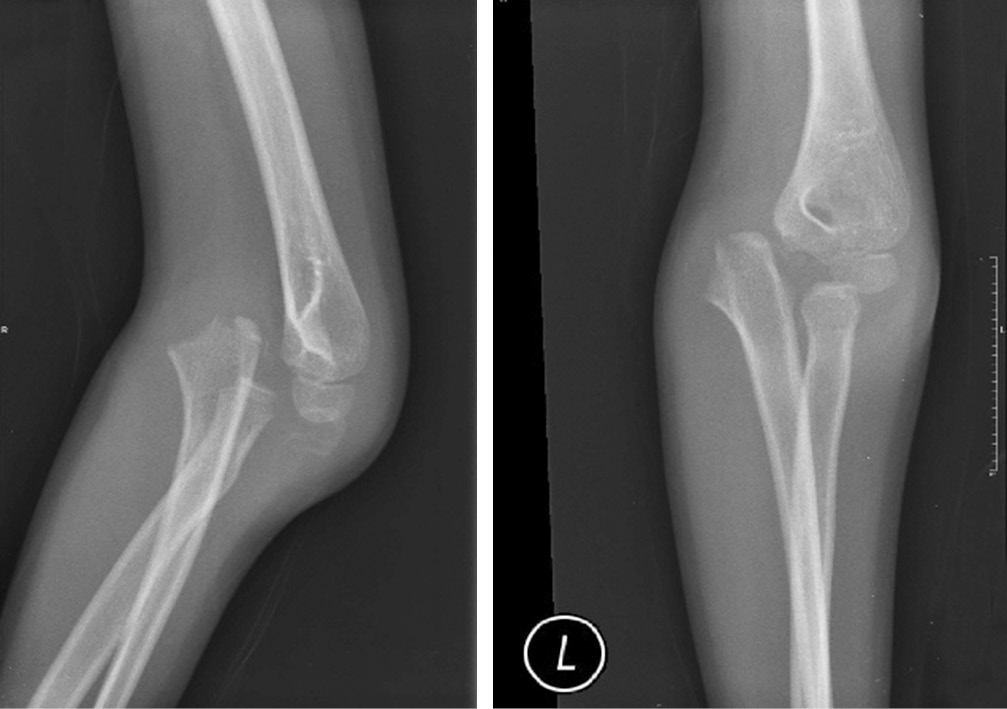

Онемение безымянного пальца и мизинца уменьшилось через неделю после операции. Симптом «когтеобразной кисти» исчез через 2 нед. Перелом зажил, и спицы Киршнера были удалены через 6 нед. (рис. 3). Осторожные пассивные движения в локтевом суставе начаты через 4 нед. с последующим присоединением активных движений через 6 нед. после операции. Лонгета была снята через 6 нед. Через 8 нед. был достигнут полный объем движений в локтевом суставе. Отмечена стабильность локтевого сустава при варусном и вальгусном стресс-тестах. Пациентка смогла вернуться к своей повседневной деятельности, и в данный момент находится под наблюдением с осмотром раз в 3 мес. (рис. 4).

Рис. 4. Объем движений в локтевом суставе через 8 нед. после операции: а — сгибание; б — разгибание; в — супинация; г — пронация